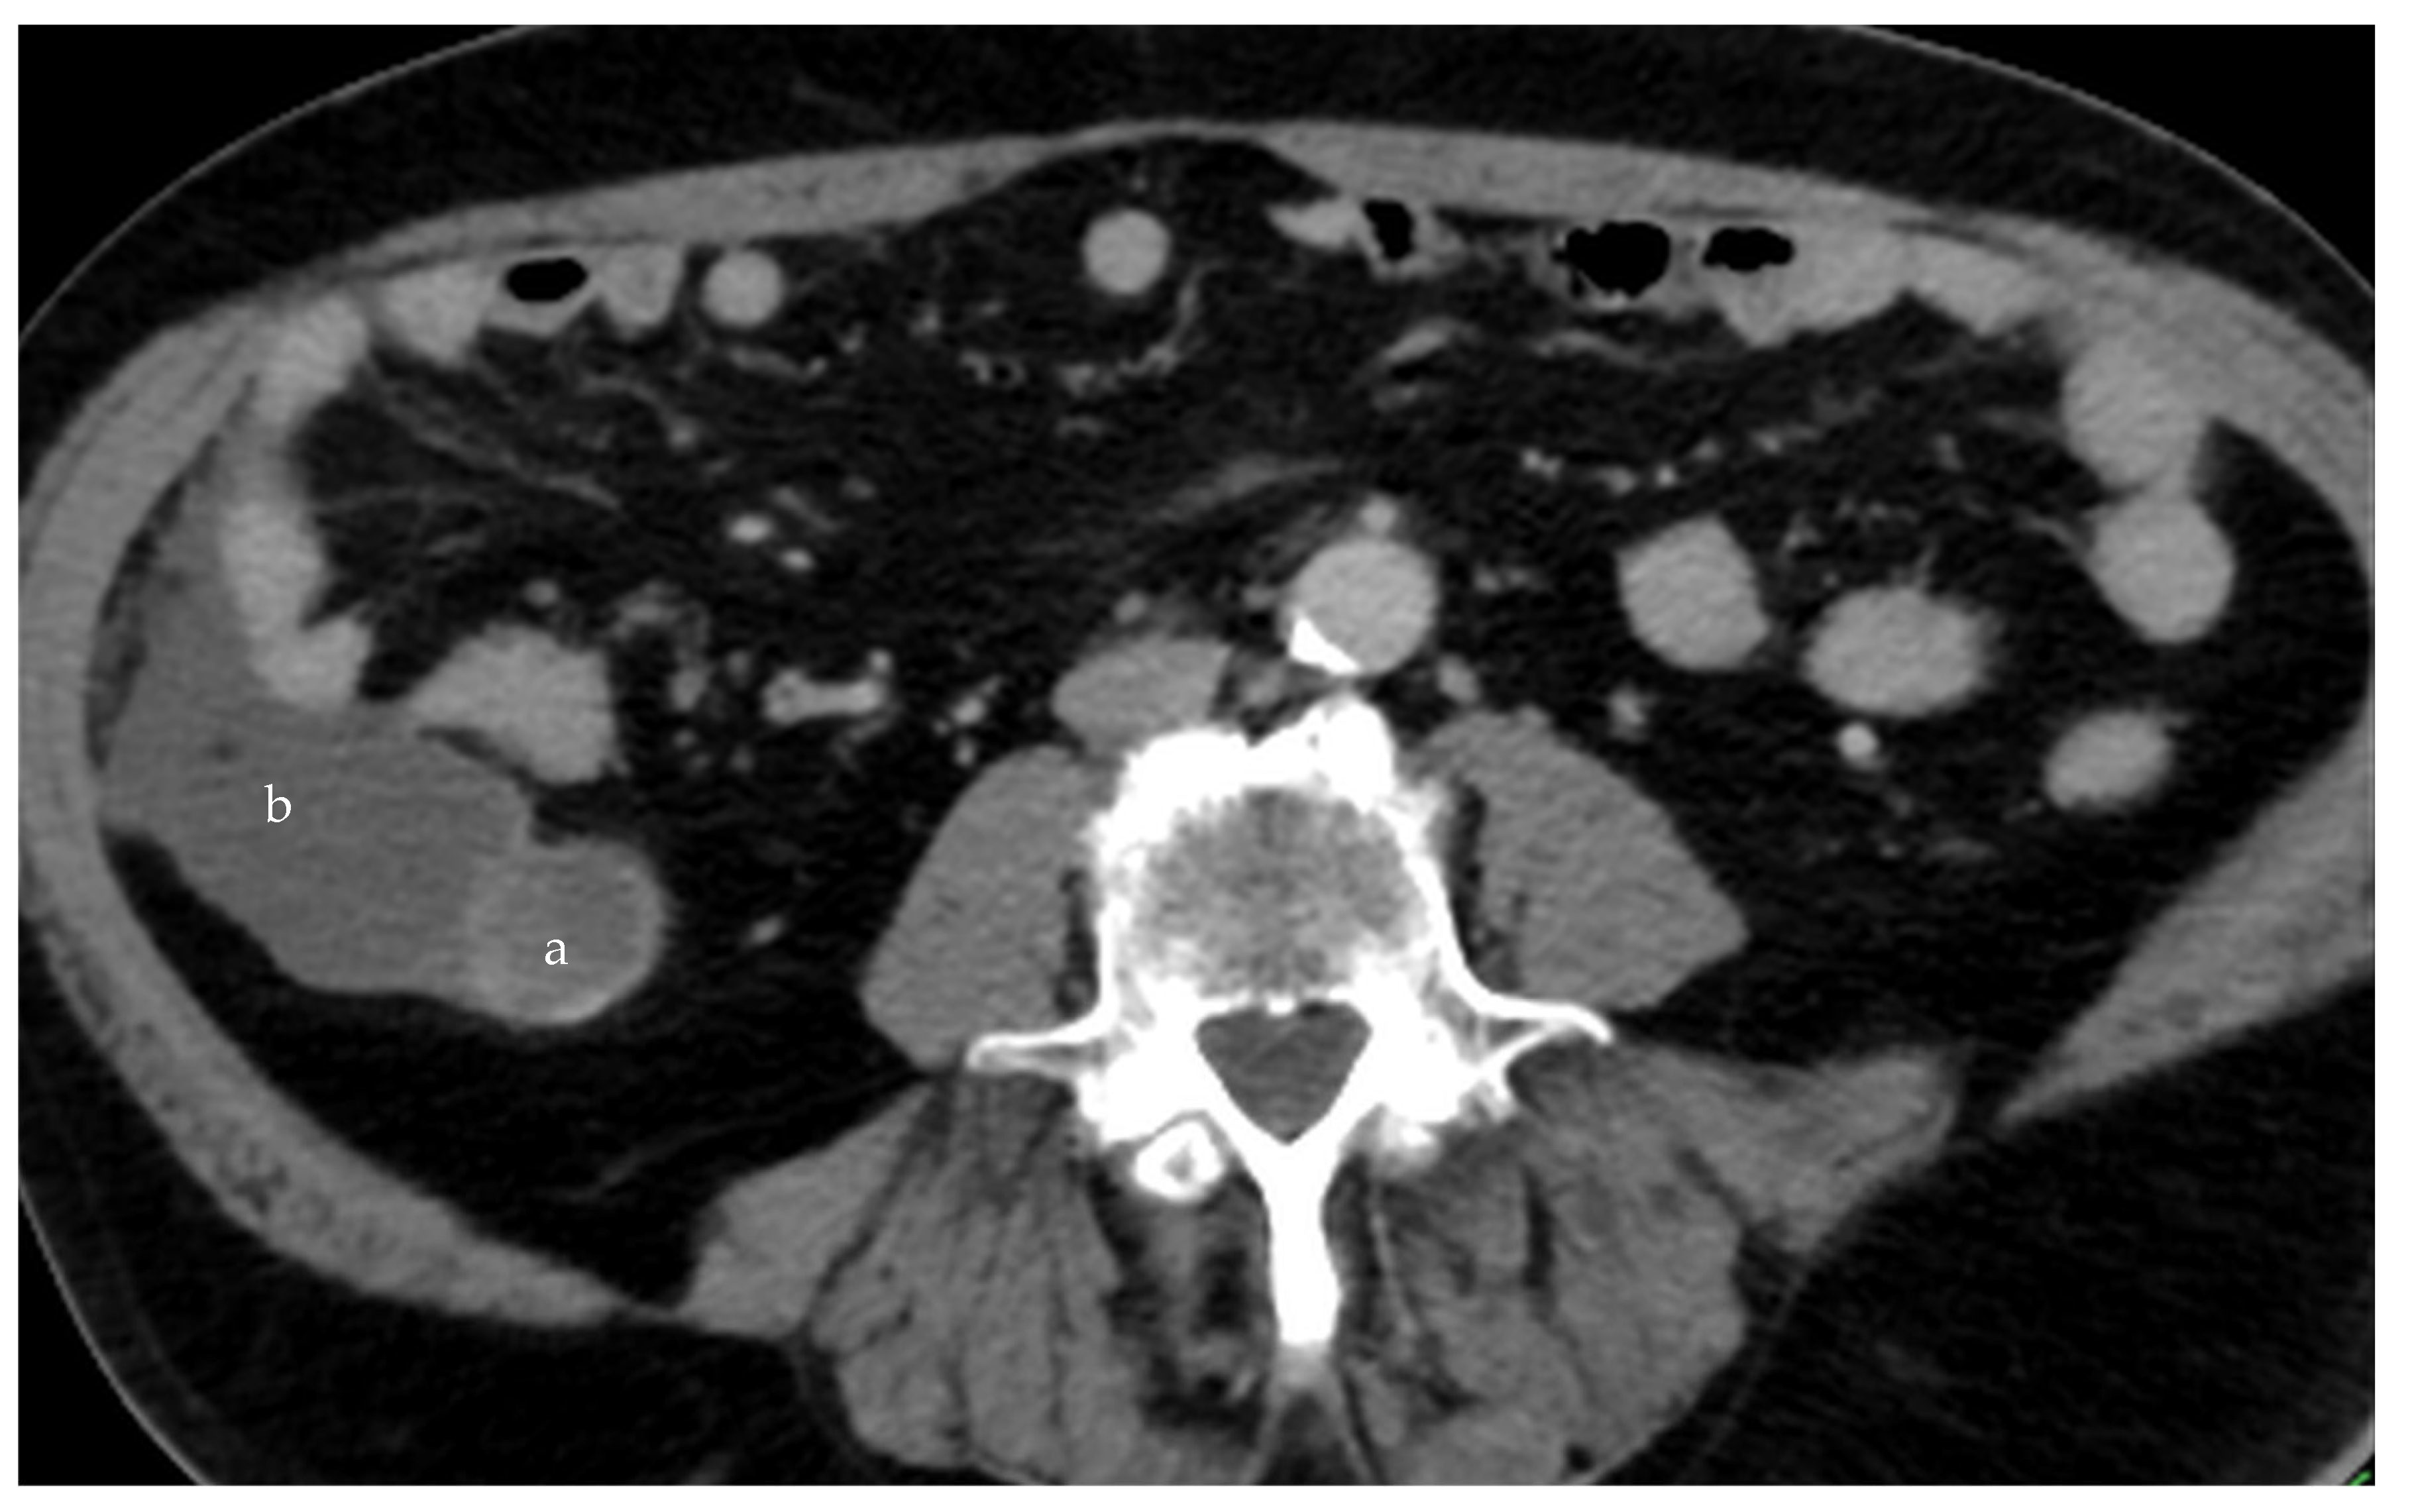

Figure 9. Ruptured mucocele of the appendix (a), with free mucin around the appendix (b) (CT, venous phase, axial plane).

The mucocele ruptures due to increased intra-appendicular pressure, releasing mucus and tumor cells into the peritoneal cavity (Figure 9 and Figure 10). The rupture may be asymptomatic or associated with only mild and nonspecific clinical signs. Typical peritoneal signs and bacterial peritonitis are usually absent because the communication to the lumen of the colon is closed by mucin. Treatment in these cases is called a radical appendectomy, with the resection of the cecal bases, but without a right colectomy. The addition of HIPEC is fully indicated. It is necessary to examine the whole abdomen to exclude the presence of tumors in typical locations, such as the Douglas pouch and the undersurfaces of the diaphragm and the right and left paracolic gutter.